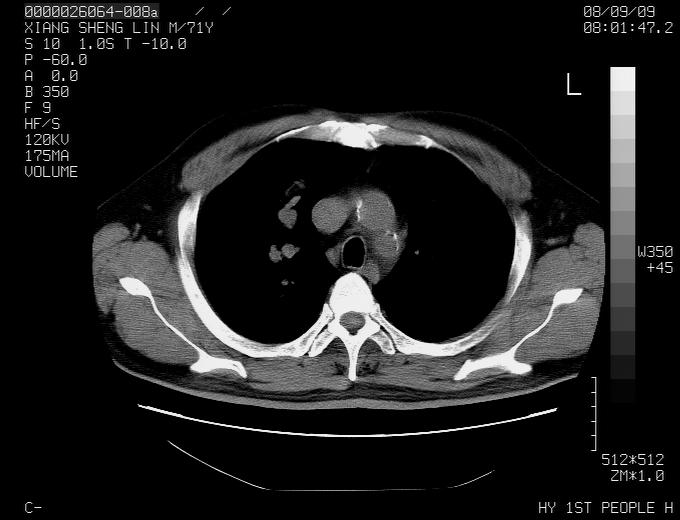

标题: CT15869:男性,71岁,因咳嗽而就诊,请讨论右上肺病变性质 [打印本页]

标题: CT15869:男性,71岁,因咳嗽而就诊,请讨论右上肺病变性质

患者,男性,71岁,因咳嗽而就诊,

典型的右肺中心性肺癌并纵隔淋巴结转移

右肺中心性肺癌并纵隔淋巴结转移可能性大!

病灶中等程度强化 还是支持肺癌诊断

考虑右肺中心性肺癌并右肺门及纵隔淋巴结转移。

1,右肺中心型ca,气管隆突旁淋巴结转移。

2,右膈明显抬高,建议肝脏扫描排除转移或原发灶。